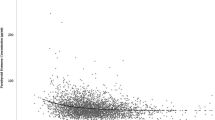

Results from 64,979 individuals, among which 42,669 (65.67%) were men and 22,310 (34.33%) were women, aged 18–89 years (50.38 ± 9.46) were included in this study (Fig. 1). The 25(OH)D and PTH were non-normally distributed while the logPTH, aCa, P, Mg showed approximate normal distributions (Supplementary Fig. 2). The mean BMI of the subjects was 25.23 ± 3.41 kg/m2, serum aCa was 2.27 ± 0.08 mmol/L, serum P was 1.21 ± 0.16 mmol/L, and serum Mg was 0.89 ± 0.06 mmol/L. The population characteristics and PTH, 25(OH)D concentrations are described in Table 1.